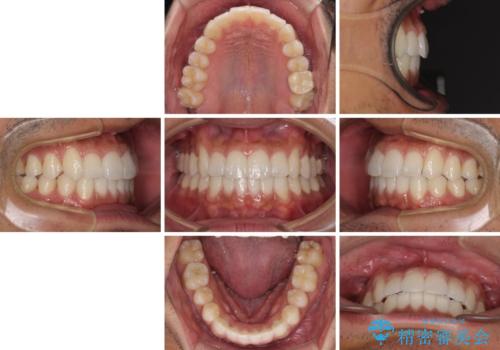

前歯のデコボコを治したい インビザライン矯正治療

- 前歯のデコボコを治したいとのことで来院された患者様です。

上下顎ともに歯列全体の後方移動とIPR(歯と歯の間を削る)によってデコボコが解消するように設計し、インビザラインにより治療を行うこととしました。

毎日22時間以上しっかりとマウスピースを装着していただいたので、スムーズに治療が進みました。歯と歯の間を削ることでうまくスペースコントロールでき、1年強で終えることができました。